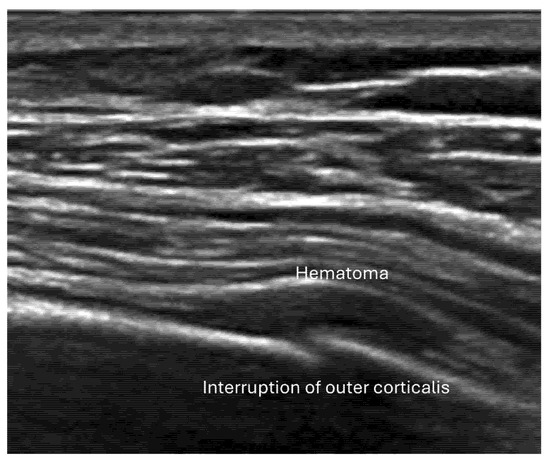

- Irregularity, interruption, or gaps in the cortical line: the cortical bone normally appears as a continuous, bright echogenic line, which is interrupted or irregular in the presence of a fracture.

- Reverberation artifacts within or adjacent to the fracture gap (also known as the “chimney sign”): these repetitive echoes are caused by ultrasound waves reflecting off the fracture surfaces.

- Local hematoma or soft tissue edema: fluid collections or increased echogenicity near the fracture site indicating bleeding and inflammation.